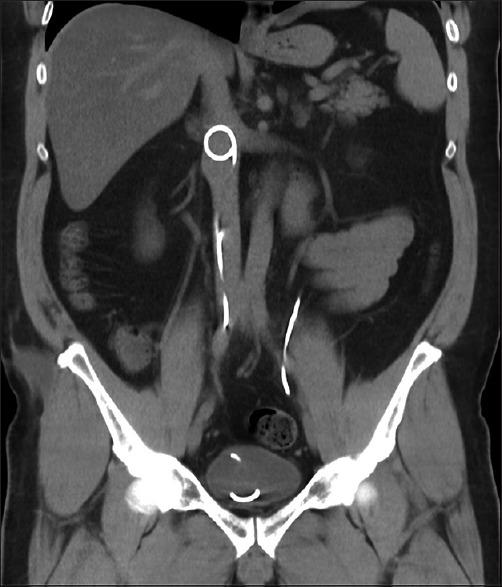

血管内双J支架移位:一例报告、综述及处理策略

A double J stent (DJS) is the main therapy for ureteral obstruction when conservative treatment fails. Antegrade migration in the bladder - or retrograde migration in the ureter - are well-known complications. We present a case with intravascular migration of a DJS into the inferior vena cava. Inferior venocavagraphy confirmed the position of the stent, and thrombus formation was excluded at its tip. The stent was retracted endoscopically. After the procedure, limited contrast leakage was seen at the perforation site on venography. The current available literature is reviewed. Based on this, a management algorithm is drawn up.

双J管(DJS)是保守治疗失败后输尿管梗阻的主要治疗方法。膀胱内顺行迁移或输尿管内逆行迁移是众所周知的并发症。我们报告一例双J管血管内迁移至下腔静脉的病例。下腔静脉造影证实了支架的位置,并排除了其尖端血栓形成。通过内镜将支架取出。术后,静脉造影显示穿孔部位有少量造影剂渗漏。本文回顾了现有的文献,并据此制定了处理流程。